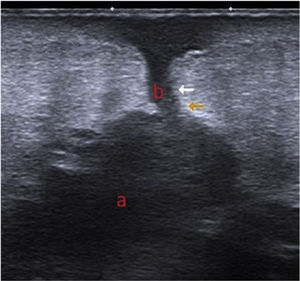

Additional TestsUltrasound revealed a hypoechoic area under the subcutaneous cellular tissue, with irregular margins and multilobular morphology (a) that communicated with the skin surface through a linear hypoechoic path (b) (Fig. 3). Scintigraphy with marked leukocytes revealed focal, progressive leukocyte deposits in the periphery of the prosthetic material in the right shoulder, particularly in the proximal region.